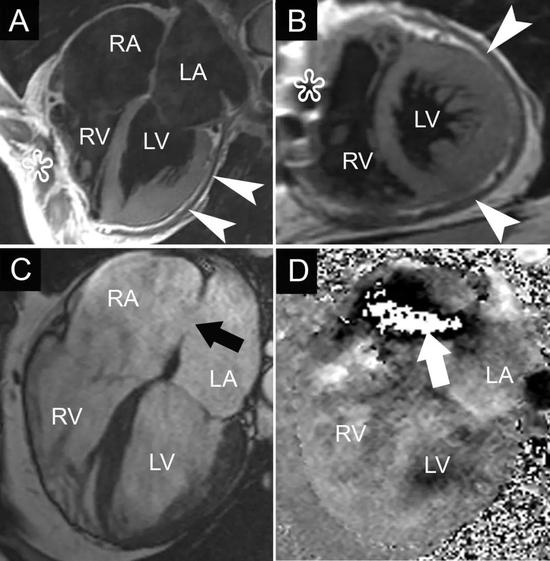

当心脏彩超检查显示总计6名受试者心脏有一些异常改变,科学家们还让这部分受试者接受了心脏磁共振检查,结果发现其中有1人出现了明显的病理性心脏改变——表现为肥厚性心肌病,而这种病是猝死的诱因之一。

通过上述结果不难看出,大众精英跑者心脏结构和功能都发生了一些适应性改变,也就是说大众跑者在大运动量作用之下,也会发生“运动员心脏”。

令人惊讶的是,本研究约有一半的受试者其单位体表面积的左房容积甚至超过了运动员正常水平的上限,左心房容积增加从本质上来说,反映了大众跑者在承受大运动量负荷时,心脏发生了不正常的形态改变,也就是说这种改变不一定是都是生理性或者健康的,有可能是病理性的。

此外,该研究还发现,有个别跑者发生了室间隔增厚,而室间隔增厚是诊断肥厚性心肌病的一种重要参考指标。

但有相当比例的跑者其心脏同样发生了病理性改变,甚至是发生了肥厚性心肌病,区分这种改变是生理性的还是病理性的,对于心脏科医生来说也并非易事。